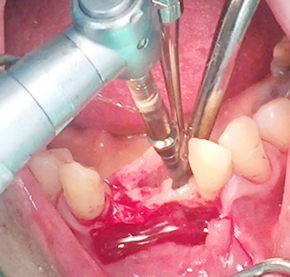

Implants/Bone Grafting

Simultaneous bone graft and implant placement